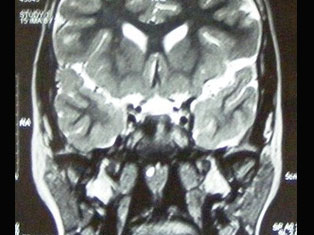

Brain Tumors

A brain tumor is a mass or growth of abnormal cells in your brain. Many different types of brain tumors exist. Some brain tumors are noncancerous (benign), and some brain tumors are cancerous (malignant).